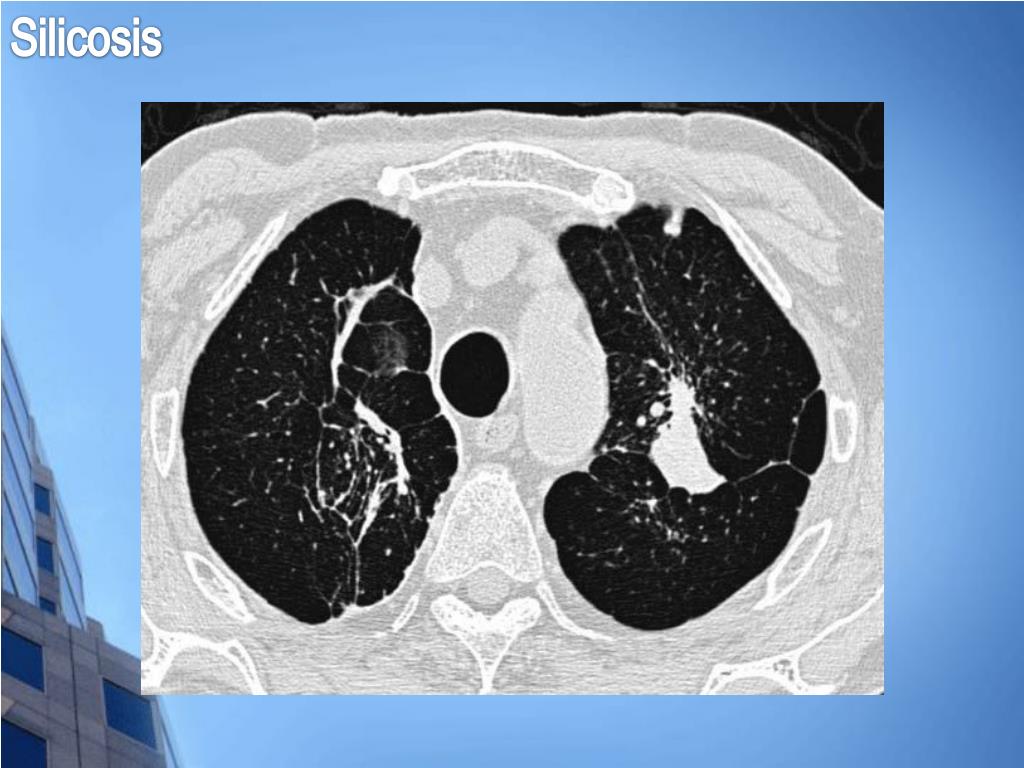

29. Silicosis

30. Silicosis Clínica • Tos • Disnea progresiva • Insuficiencia respiratoria • Cor pulmonale • Pueden faltar los crepitantes bibasales • Síndrome de Caplan: pacientes con artritis reumatoide; nódulos necrobióticos sobre los nódulos de la silicosis simple.

31. Silicosis

32. Silicosis

33. Silicosis

34. Silicosis Formas clínicas • Silicosis aguda o silicoproteinosis: forma aguda y rápida de progresión de la enfermedad. Exposición a concentraciones elevadas de sílice, presentándose a los 1 – 3 años. Mal pronóstico. • Silicosis acelerada: clínicamente similar a la aguda pero radiológicamente a la crónica. Suele aparecer entre 5 – 10 años de exposición. • Silicosis simple: historia laboral, sin clínica. Suele aparecer a los 20 años. Opacidades redondeadas. No suele asociarse a repercusión cardíaca y leve disminución de parámetros respiratorios. • Silicosis complicada: grandes opacidades redondeadas de Fibrosis Masiva Progresiva. En estadios avanzados progresa a todas las complicaciones de una fibrosis pulmonar.